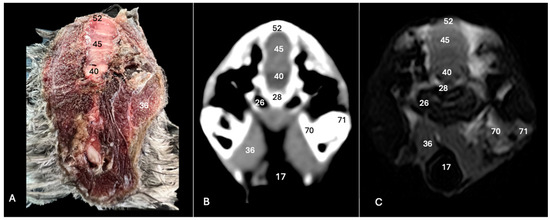

Cory’s Shearwater (Calonectris borealis): Exploring Normal Head Anatomy through Cross-Sectional Anatomy, Computed Tomography and Magnetic Resonance Imaging

3. Result

3.1. Anatomical Sections

3.2. Computed Tomography (CT)

3.3. Magnetic Resonance Imaging (MRI)